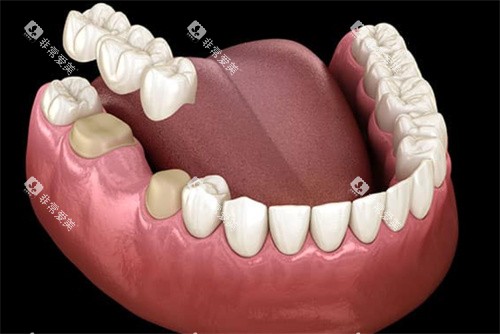

活动义齿是可自行摘戴的修复体,适用于单颗或多颗牙齿缺失的情况,是价格更为亲民的缺牙修复方式。

活动义齿更大优势在于价格便宜、制作周期短,且适用范围广,即使是多颗或全口牙齿缺失也能修复。然而,其缺点也十分明显:需要每天摘戴清洗,无法承受较大咬合力,对患者咬合功能帮助有限。普通树脂活动义齿耐磨性较差,使用年限较短,通常几年后便需更换。

活动义齿特别适合经济预算有限、全身健康状况不适合做固定修复的患者,或作为临时修复体使用。对于牙槽嵴重的吸收的全口无牙颌患者,活动全口义齿往往是独一选择。